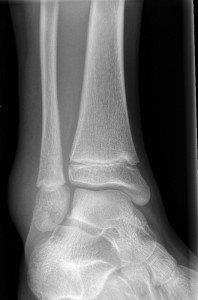

Fractures suitable for Controlled Ankle Motion (CAM) boot use are usually sustained with inversion injuries of the ankle. Twisting injuries may cause a toddler’s fracture in younger children.

Swollen and tender lateral malleolus or base of fifth metatarsal.

Avulsion fracture of distal fibula

Salter Harris I fracture of fibula

Undisplaced Salter Harris II fracture of fibula

Undisplaced epiphyseal fracture of distal fibula